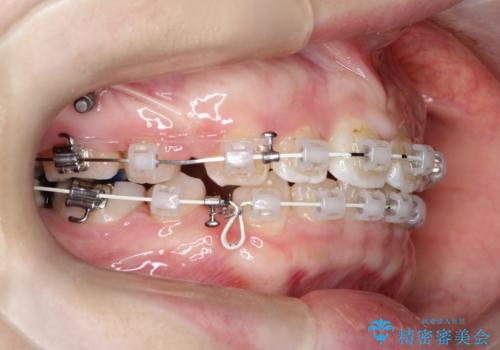

上下左右小臼歯を抜歯して審美装置で治療を行いました。

抜歯したスペースをきちんと下げることができるように、矯正用のアンカースクリューを用いて治療をしております。